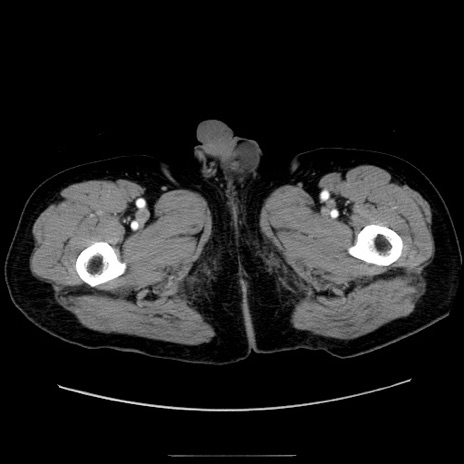

症例30(横断像)

【症例】80歳代男性

【主訴】臍周囲痛

【現病歴】約6時間前から臍下部痛が出現。次第に腹部膨隆・背部痛も生じてきたため来院。背部痛の場所は変化しない。

【既往歴】腎盂腎炎

【身体所見】意識清明、BT 36.3℃、BP  131/87mmHg、P 87bpm、SpO2 100%(RA)、臍周囲自発痛・圧痛あり、反跳痛なし、自発痛部位に一致して板状硬あり、腹部膨隆、腸雑音減弱、CVA tenderness両側陰性。

【データ】WBC 19600、CRP 0.33